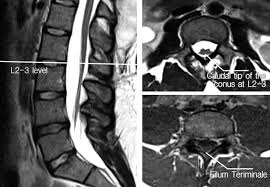

Tethered cord syndrome in adults indications. Tethered cord syndrome TCS is rare but no one knows exactly how prevalent it is because it commonly goes undiagnosed. Adult tethered cord is determined by an MRI which shows a low level of the conus medullaris below L2 and thickened filum terminale. Less qualifiers are acceptable with indirect imaging findings.

Indications techniques and long-term outcomes in. Adult tethered cord is determined by an MRI which shows a low level of the conus medullaris below L2 and thickened filum terminale. The occult tethered cord syndrome and surgical indication - PEDs Neuro Ortho UroGI Progressive Syringohydromelia Filum 2mm in axial section Derm ¾ clinical qualifiers mandatory for surgical indication. In adults symptoms are aggravated by trauma maneuvers associated with stretching of the spine flexion disc herniation and spinal stenosis. J Neurosurg Spine 42123-1312006. The tethering effect was caused either by a split cord malformation a thick filum terminale a conus medullaris lipoma with extradural extension or various combinations of these mechanisms. The authors performed a retrospective study of clinical outcomes after neurosurgical intervention in 60 adults with TCS. Of the 2515 patients 85 adults with a tethered cord syndrome formed the basis of this study. In the present study we analyzed the data of patients who presented with TCS in adulthood with the aim of studying the clinical spectrum and management strategies.